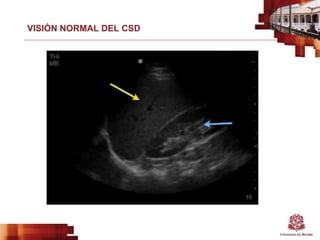

VISIÓN NORMAL DEL CSD

VISIÓN ANORMAL DEL CSD